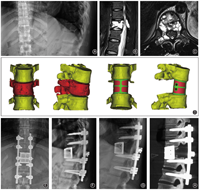

通过对CT和MRI检查图像数据进行3D重建和融合,获得脊柱肿瘤的3D模型数据集。辨识肿瘤,获得肿瘤大小、位置、性质以及与周围正常组织和异常增生血管的毗邻关系等信息。利用3D打印技术制备模型,获得对病灶区空间关系更清晰直观的认识。

根据不同病变节段和病椎形态进行个性化设计,上下终板前后径、左右径和上下终板角度均与患者椎体缺损形成个体化匹配。人工椎体采用多孔结构和实心桁架相结合的结构提升人工椎体的力学强度。椎体中央设计植骨孔道,椎体背面为光滑结构避免与硬膜粘连,椎体两侧设计有可供夹持和术中调整的夹持孔(图1)。采用激光选区熔融的工艺进行加工,加工后进行后处理、清洗和灭菌消毒,备术中使用。

术后随访6个月按Brantigan-Steffee的影像学融合标准判定为全部融合(图2),融合有效率为100%[95%CI(75.6%,100%)],95%CI下限大于预设目标值70%,人工椎体产品的有效性满足临床要求。

术前、术后第15天、术后3个月及术后6个月椎体间高度分别为32.75(25.94,68.20)、41.09(30.55,70.20)、40.70(30.23,67.83)和40.74(30.23,67.08) mm,差异无统计学意义(χ2=0.768,P=0.857,图3)。